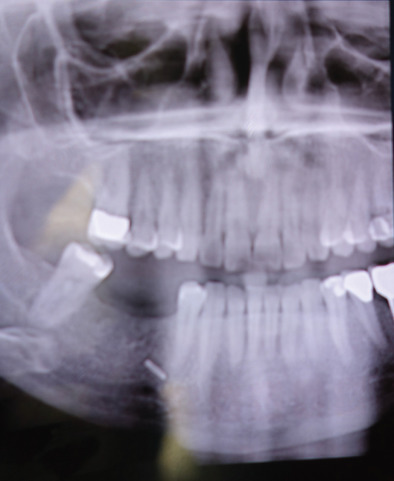

With or without a repair, if forehead and anterior scalp pain persist despite scar massage, neuropathic pain medication, and steroid injection, then a surgical approach to the painful neuroma is appropriate. This is illustrated in Fig. 3.15.11 . After protecting the globe, and injecting the local anesthetic, an upper eyelid incision is made, taken deep to the orbicularis muscle, and then the dissection is directed along the orbital septum to the superior orbital rim. The branches of the supraorbital nerve are identified within the orbit, blocked with 1% lidocaine with epinephrine, dissected about 1.5–2 cm into the orbit, cauterized with a bipolar coagulator set at low level, and then sharply divided with a microscissors, allowing the proximal end to retract into the orbit and above the orbital fat. The supratrochlear nerve is treated in a similar manner, taking care not to injure the superior oblique muscle as it courses around the trochlea. My personal experience with the first 5 patients having this approach has been reported. The mean preoperative pain (VAS) was 9 and the mean postoperative pain level was 0.6 (p <.001). The mean follow-up was 19.6 months, range 12–34 months. There were no surgical complications ( Table 3.15.1 ). This experience has been confirmed since then with two more patients.